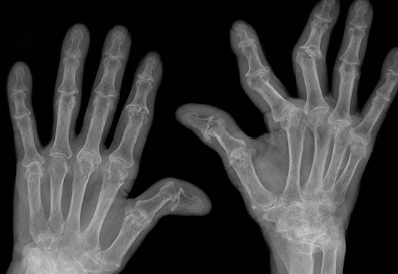

류마티스 관절염은 관절 활막이라는 조직에 염증이 생기는 만성 질환으로, 손과 발의 작은 관절에 통증과 부기, 뻣뻣함 등의 증상이 나타납니다. 류마티스 관절염은 완치할 수 없는 질환으로, 잘못 치료하면 관절이 손상되거나 변형되어 일상생활에 큰 불편을 겪을 수 있습니다.

이러한 증상이 6주 이상 지속되면 류마티스 관절염을 의심해야 합니다. 의사와 상담하여 혈액 검사나 X-ray 검사 등을 통해 정확한 진단을 받아야 합니다.

류마티스 관절염은 관절 주위를 둘러싸고 있는 활막이라는 조직의 염증으로 인해 발생하는 만성 염증성 질환입니다. 이 질환은 활막이 존재하는 모든 관절, 즉 움직일 수 있는 거의 모든 관절에서 발생할 수 있으며, 손과 발의 작은 관절에 좌우 대칭적으로 관절염이 생기는 것이 특징입니다. 류마티스 관절염은 주로 40대에서 70대 사이의 여성에게 많이 발생하며, 우리나라의 유병률은 약 0.5~1.0%로 추정됩니다.

류마티스 관절염의 초기 증상은 주로 손마디가 뻣뻣해지는 것입니다. 특히 아침에 자고 일어난 직후에 이 증상이 심하게 나타납니다. 1시간 이상 관절을 움직여야만 뻣뻣한 증세가 풀립니다. 이와 동시에 환자들은 손마디가 붓고 통증이 느껴져 손을 쓸 수 없다고 호소합니다. 관절염이 무릎이나 팔꿈치, 발목, 어깨, 발까지 침범하는 경우도 흔합니다. 통증이 있는 마디를 만지면 따뜻한 열감을 느낄 수 있습니다.